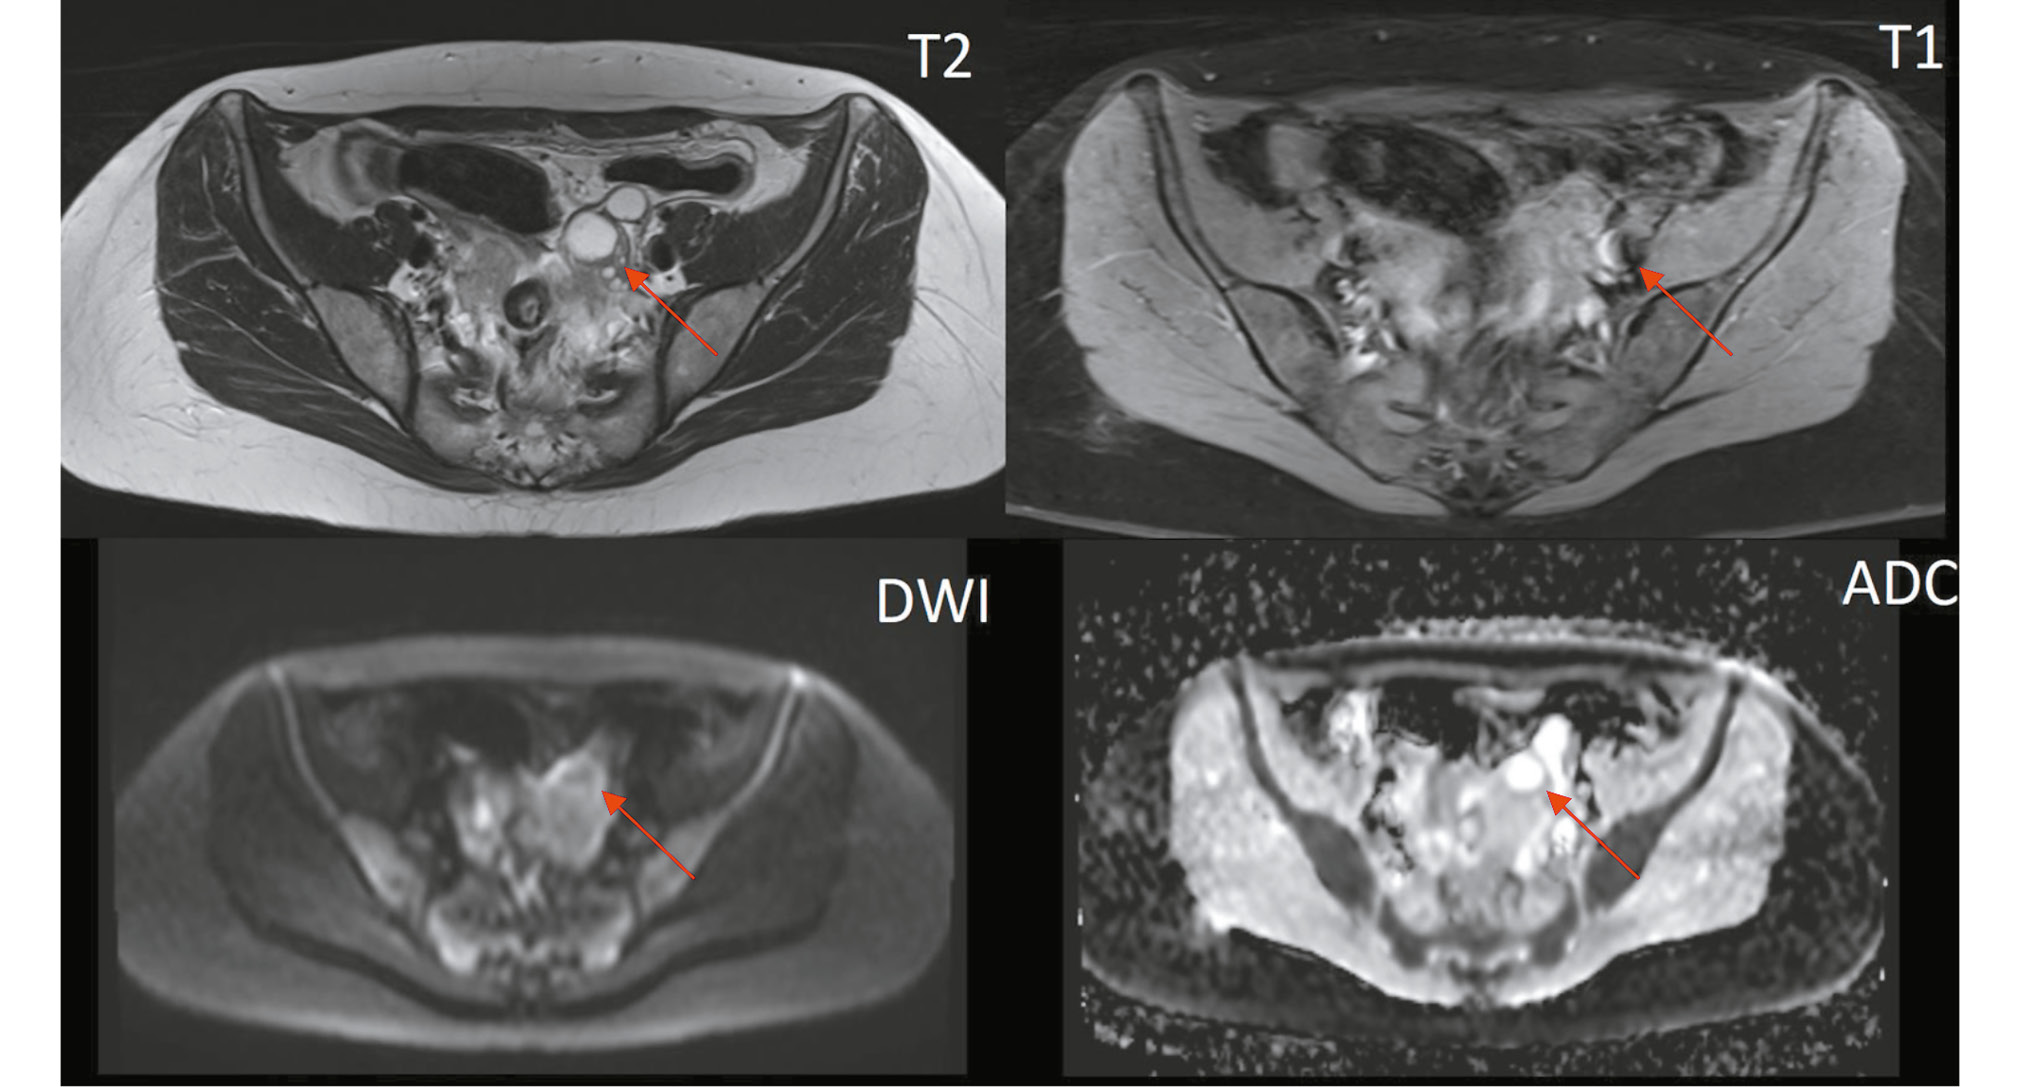

A tubular structure with high fluid signal intensity and an irregular lumen, measuring up to 17 mm, was located adjacent to the anterior and outer contours of the right ovary. This structure had multiple hypervascular solid nodules on the walls and showed signs of restricted diffusion in the DWI sequence (Fig. 4). A smaller structure with similar MRI characteristics was observed on the left (Fig. 5).

Fig. 4. Pelvic magnetic resonance imaging (axial view). The right fallopian tube contains fluid and solid nodules, with signs of restricted diffusion on DWI mode (red arrow).

Fig. 5. Pelvic magnetic resonance imaging (axial view). Similar solid nodules are present in the left fallopian tube (red arrow). The right fallopian tube appears convoluted in this slice (blue arrow).

- Oblong or tubular lesions in the adnexal area, often with relatively uniform fluid signal intensity (low on T1WI and high on T2WI). In our case, the lesion contained several solid foci on the walls, clearly visible against the backdrop of the distended fallopian tube. These solid foci showed restricted diffusion on DWI/ADC and early contrast uptake in the dynamic contrast-enhanced sequence.

- Fluid in the fallopian tubes (hydrosalpinx): This condition results from tumor secretions that block the fallopian tube, causing colic-like pelvic pain due to stretching. The contents of the hydrosalpinx can vary, leading to different MRI signals. In our case, the fallopian tubes were distended with serous fluid, although a hemorrhagic component due to recurrent bleeding is also possible.